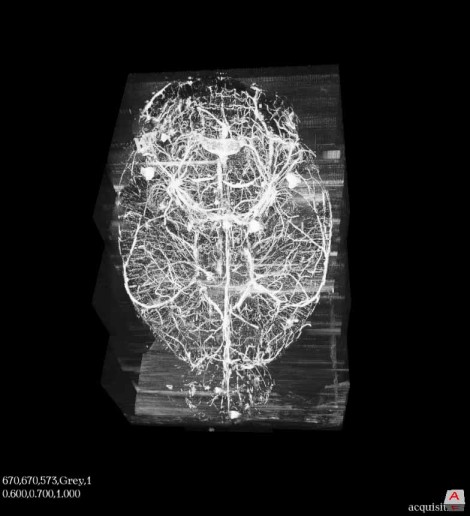

Spatial biology within tissue samples is very complex and very difficult to understand these images in 2D, at 3Scan the scans are converted into 3D models for a more detailed look. With the KESM, 3Scan are the first histopathologists able to render 3D imagery based on micron level scans. The speed and precision of this technology enables a faster and more accurate diagnosis and, in some cases, earlier detection and management of disease.

Computing biological differences within an organ, or between organisms, is especially useful for animal models used in pre-clinical drug discovery research in a pharmaceutical trial. This enables quantification of microvasculature and may provide insight into various diseases, such as Alzheimer’s, diabetes, and cancer. By examining large volumes of tissue at maximum light microscopy resolution with high throughput, scientists and pathologists can improve the accuracy of morphological assessment and identification of normal and diseased tissue states.

By combining sectioning and imaging into a single step, a large part of the traditional pathology workflow is automated. This allows for a greater speed, precision, throughput, and scale at which tissues are digitized. To handle high-resolution data of over a terabyte per cm3, sophisticated data processing software is applied to model 3D tissue reconstructions, providing interactive image views, and applying quantitative analytics. This allows quantitative analysis to be performed on 3D image stacks of whole mouse organs, which is extremely difficult, expensive, and time-consuming with traditional manual techniques due to the size and lengthy experiments. Mouse organs are heavily relied on in academic research and early pharmaceutical research; they are beneficial in the pre-clinical phase of pharmaceuticals and are critical to advancing medical research.